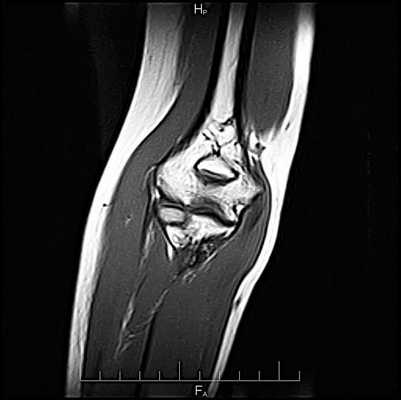

МРТ локтевого сустава в продольной проекции в норме

Серия Т1-взвешенных томограмм правого локтевого сустава во фронтальной проекции с направлением срезов от заднего отдела к переднему. Сухожилие трехглавой мышцы прикрепляется к локтевому отростку. Начинают хорошо визуализироваться локтевая мышца и глубокий сгибатель пальцев. На срезе появляются сухожилия локтевого сгибателя запястья и локтевого разгибателя запястья. Серия Т1-взвешенных томограмм левого локтевого сустава во фронтальной проекции с направлением срезов от заднего отдела к переднему. Сухожилие трехглавой мышцы прикрепляется к локтевому отростку. Начинают хорошо визуализироваться локтевая мышца и глубокий сгибатель пальцев. На срезе появляются сухожилия локтевого сгибателя запястья и локтевого разгибателя запястья. Позади медиального надмыщелка можно увидеть локтевой нерв. Латеральная локтевая коллатеральная связка формирует петлю позади шейки лучевой кости, обеспечивая заднелатеральную стабилизацию. Общее сухожилие разгибателей длинное и тонкое, тогда как общее сухожилие сгибателей — короткое и широкое. Позади медиального надмыщелка можно увидеть локтевой нерв. Латеральная локтевая коллатеральная связка формирует петлю позади шейки лучевой кости, обеспечивая заднелатеральную стабилизацию. Общее сухожилие разгибателей длинное и тонкое, тогда как общее сухожилие сгибателей — короткое и широкое. Лучевой нерв проходит между плечевой и плечелучевой мышцами. Дистальный отдел сухожилия двуглавой мышцы приближается к месту своего прикрепления к бугристости лучевой кости. Хорошо видны контуры бугристости лучевой кости. Плечевая мышца покрывает переднюю поверхность тела плечевой кости. Лучевой нерв проходит между плечевой и плечелучевой мышцами. Дистальный отдел сухожилия двуглавой мышцы приближается к месту своего прикрепления к бугристости лучевой кости. Хорошо видны контуры бугристости лучевой кости. Плечевая мышца покрывает переднюю поверхность тела плечевой кости. Круглый пронатор огибает переднюю поверхность предплечья. Сухожилия плечевой и двуглавой мышц визуализируются на пути к местам прикреплений. Лучевой нерв разделился на поверхностную и глубокую ветви. Срединный нерв проходит латеральнее круглого пронатора. Круглый пронатор огибает переднюю поверхность предплечья. Сухожилия плечевой и двуглавой мышц визуализируются на пути к местам прикреплений. Лучевой нерв разделился на поверхностную и глубокую ветви. Срединный нерв проходит латеральнее круглого пронатора. Из мышц предплечья все еще визуализируется только плечевая мышца. Все еще визуализируется двуглавая мышца плеча. Непосредственно ниже подкожной жировой клетчатки все еще прослеживаются двуглавая мышца плеча и латеральная подкожная вена руки. Из мышц предплечья все еще визуализируется только плечевая мышца. Все еще визуализируется двуглавая мышца плеча. Непосредственно ниже подкожной жировой клетчатки все еще прослеживаются двуглавая мышца плеча и латеральная подкожная вена руки.